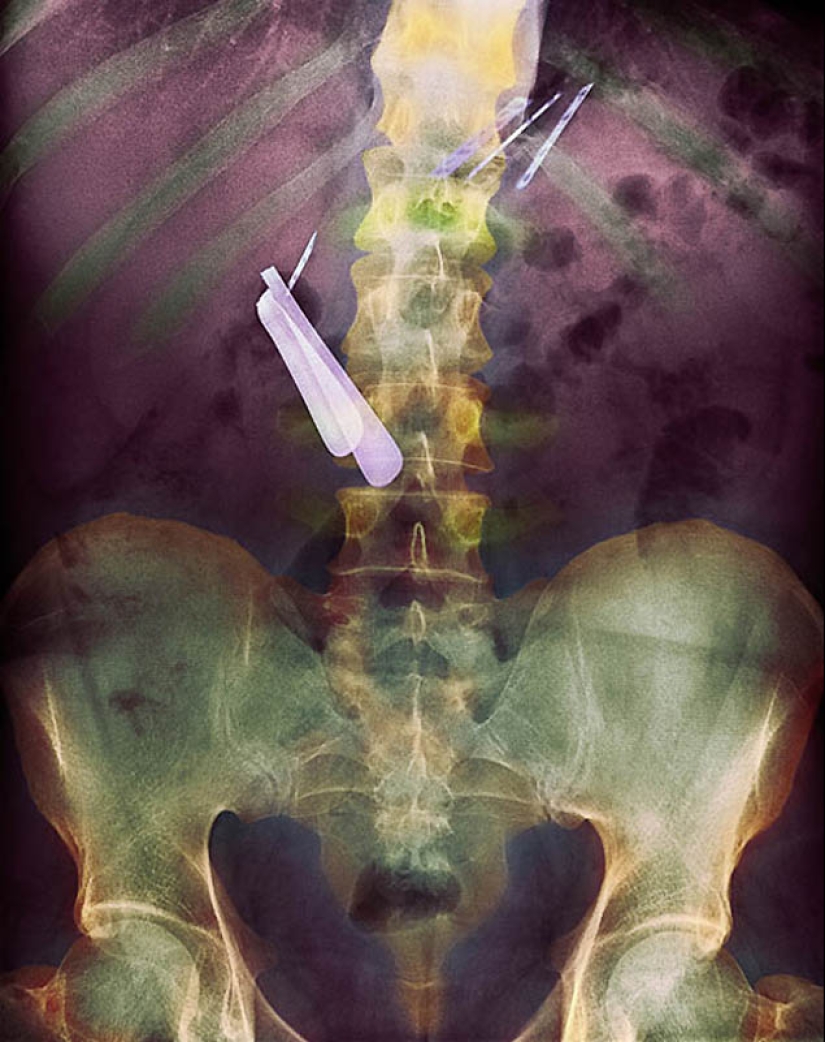

8. Radiografía a color del estómago del paciente que ingirió la maquinilla de afeitar (centro izquierda) y la cuchilla (parte superior derecha).